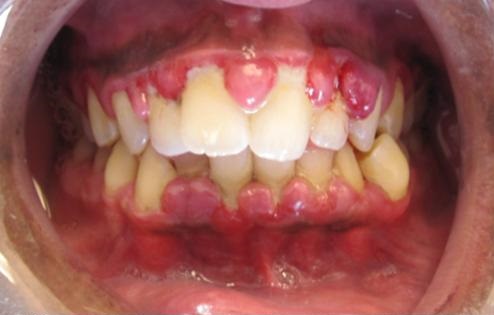

- Ούλα που αιμορραγούν

Ούλα που ματώνουν κατά το βούρτσισμα των δοντιών, ή κατά τη χρήση οδοντικού νήματος. Η αιμορραγία των ούλων κατά τη εφαρμογή της στοματικής υγιεινής ή και αυτόματα, αποτελεί μια από τις πιο σαφές ενδείξεις ουλίτιδας. Δυστυχώς πολλοί ασθενείς συνεχίζουν να αγνοούν τα συμπτώματα της ουλίτιδας, ενώ αρκετοί όταν αντιληφθούν το μάτωμα των ούλων αρχίζουν να αποφεύγουν το βούρτσισμα επιδεινώνοντας την κατάσταση, αντί να βουρτσίζουν ακόμη περισσότερο και να επισκεφθούν άμεσα τον οδοντίατρο τους όπως χρειάζεται.

Κόκκινα, στιλπνά ούλα

Τα υγιή ούλα έχουν ένα φυσιολογικό σχεδόν ροζ χρώμα και ματ επιφάνεια. Αν αποκτήσουν έντονο κόκκινο χρώμα ή γίνουν στιλπνά, αυτό προδίδει πρόβλημα ερεθισμού και είναι το πρώτο σύμπτωμα ουλίτιδας